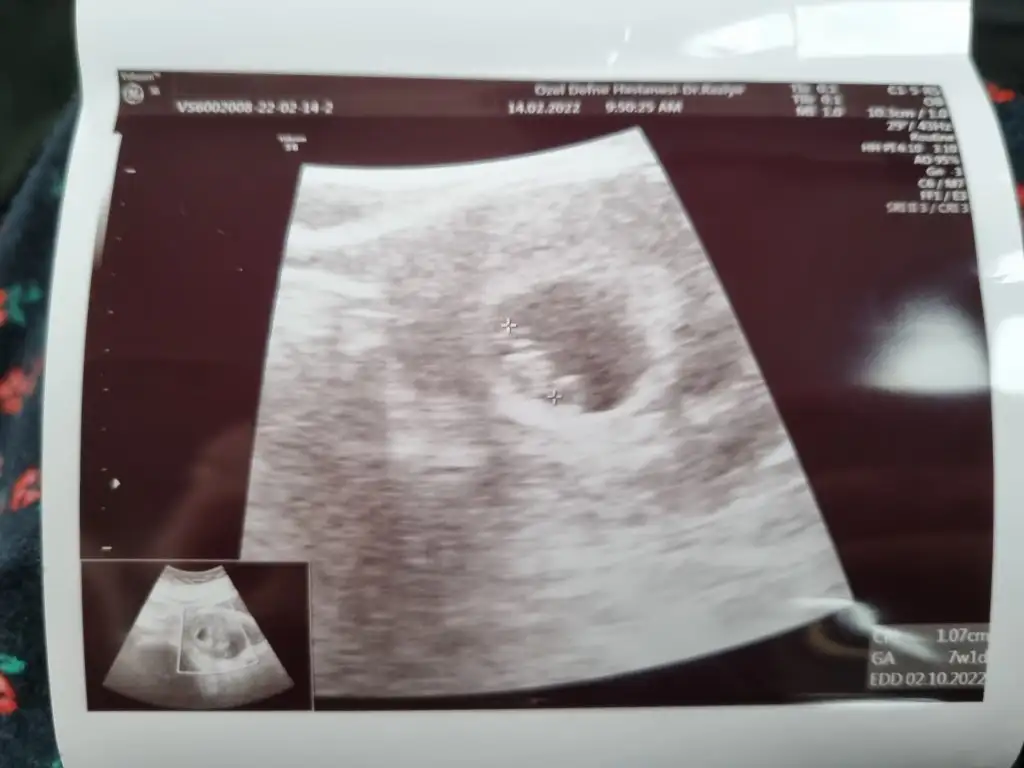

Verdi canim benimki minik ve artistik bir pozda ayakta duruyor gibi 😅 7+1 çıktı ultrasonda 1 gün geri sadece 🥰

• 20220214_100637.webp

20220214_100637.webp

21,6 KB · Görüntüleme: 75

8+1 dedi ebe. Son adetle uyumlu yani. Gelişimi de iyiymiş. Bu haftadan sonra düşük olma iht %10 a düştü dedi.